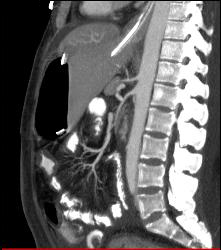

Thickened Small Bowel Loops With Mesenteric Inflammation